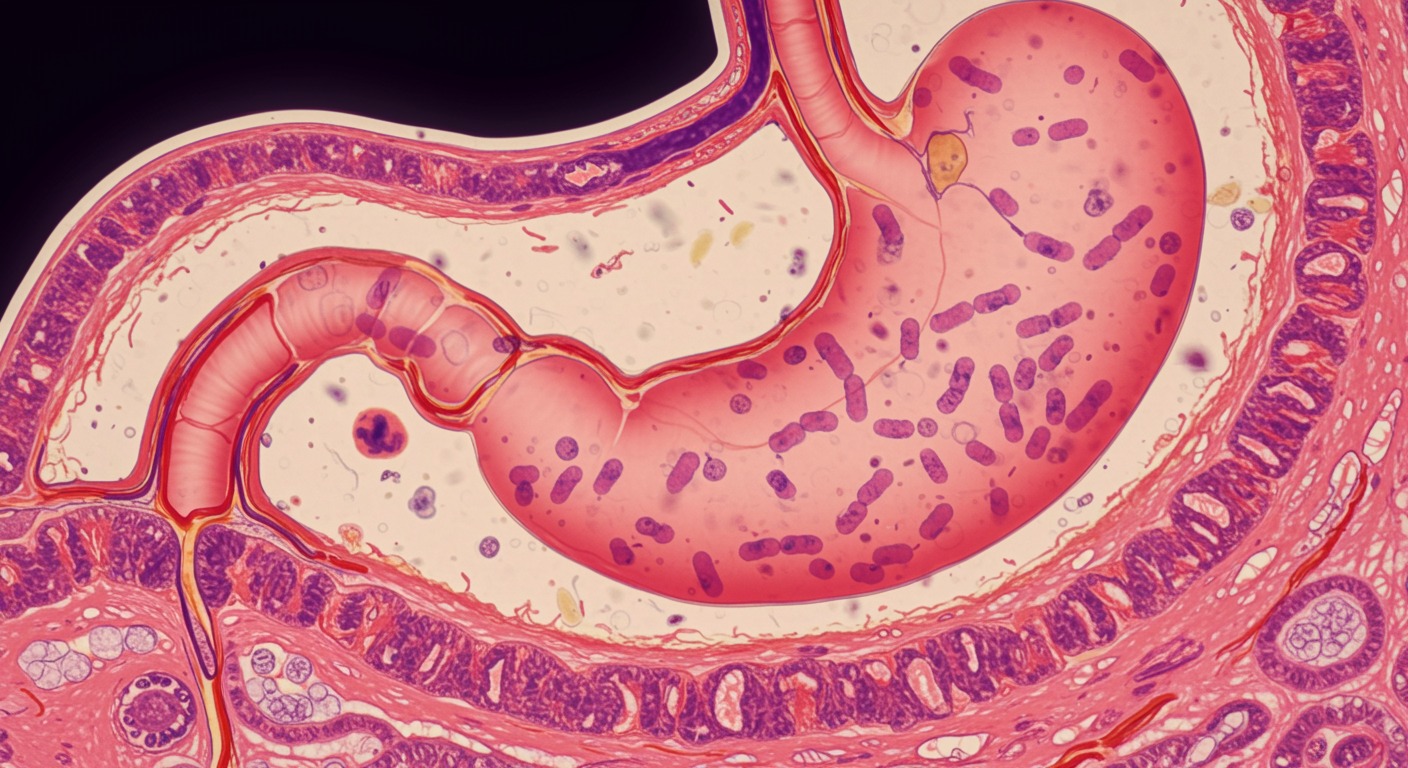

The gastrointestinal system—from mouth to colon—is responsible for digestion, nutrient absorption, immune function, and even neurotransmitter production. As the interface between the external environment and the internal body, gut health has far-reaching effects on overall wellness.